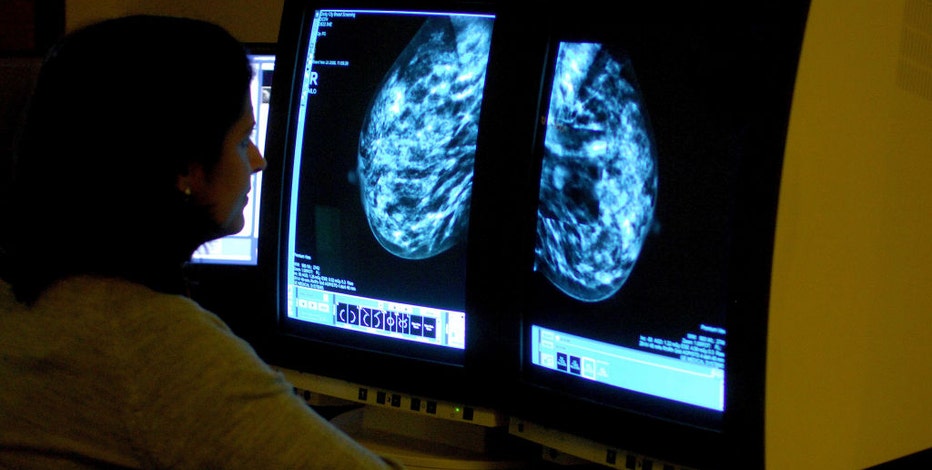

FILE - A file image shows a consultant analyzing a mammogram showing a womans breast in order check for breast cancer. (Photo by Rui Vieira - PA Images/PA Images via Getty Images)